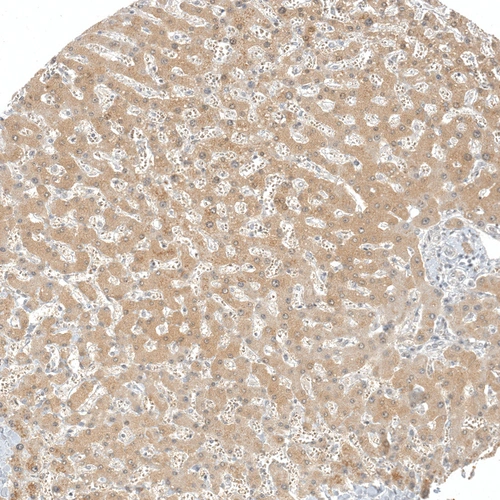

Immunohistochemical staining of human liver shows moderate cytoplasmic positivity in hepatocytes.